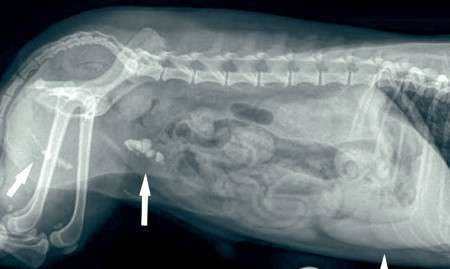

В экстренном порядке больным с мочекаменной болезнью (подозрением на этот диагноз) проводят УЗИ органов брюшной полости. Благодаря этому исследованию ветврач получает данные об их актуальном состоянии, определяет показатель содержания взвесей в мочевом пузыре, мочевыводящих протоках или почках питомца. Если имеются косвенные признаки камнеобразования, кошке может проводиться рентгенография с применением/без применения контрастного вещества. Для оценки состояния почек пациентам с МКБ дополнительно может назначаться ОАК и биохимия.

У кошек и собак (сук), чаще диагноз мочекаменная болезнь ставится когда

образуется камень в мочевом пузыре или почках, что сопровождается не

поддающимися лечению, повторяющимися кровотечениями и подтверждается

рентгеновским снимком или УЗИ.